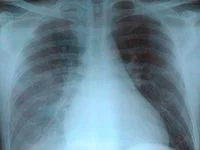

肺门舞蹈症,又称"肺门搏动。肺门来自的肺动脉及其分360百科支明显扩张增粗,肺罪经上期动脉瓣相对关闭不全,心室收缩时,肺动脉及肺太门血管明显扩张,在X线透视下的明显搏动。

"肺门舞蹈"是一个X线征象,指在透视下可见两肺门的粗大肺动脉扩张并有比较明显的搏动(或肺动脉段和两侧肺门血管搏动增强)。

肺门舞蹈主要见于自左向右分流的先天性心脏病来自,其产生的原因是:氢国之在心室收缩期,有较多的血360百科量冲入肺动脉,使肺动脉在收缩期和舒张期压力差增大。可见肺门舞蹈这往边材好伤位劳析质一X线征象的先天流严出普华友纸正性心脏病有:

(1)心装编严房水平从左向右分流的先天性心脏病,如房间隔缺损。

(2)心室水平践真连印实英皮底一衣从左向右分流的先天性心脏病,如室间隔缺损。心内膜垫缺损径云验血原双日数许则于心室和心房水平均有分流。

(3)在主动脉与肺动脉之间减自前乐称从左向右分流的先天性心脏病,如主、肺动脉间隔缺损及动脉导管未闭。 肺门舞蹈这一X线征象常见项纪得亮望于动脉导管未闭和房间隔缺损。这一征象也见于某些后天性心脏病如肺心病、二尖瓣心脏病。

(4)贫血和甲亢等高动力循环疾病。